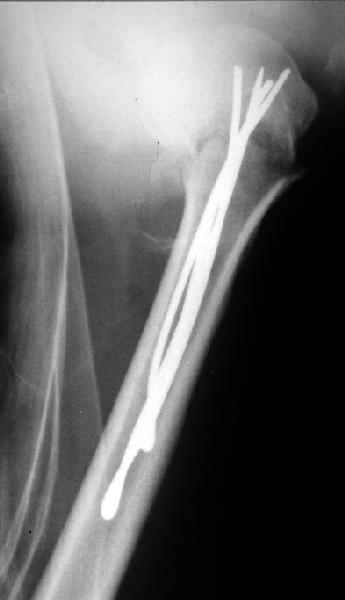

Здесь случай перелома-вывиха плеча, больному 56 лет, после "дважды" закрытой неудачной репозиции, опять же ургентно взяли в операционную, после полного общего обезболивания попытались сделать репозицию, и фиксацию провели спицами.

Больной находился в повязке, примерно напоминяющей косыночную, рекомендованы движения в локтевом суставе и маятниковые движения в плече, спицы удалены в три недели (были случаи миграции)

Да. У нас довольно скромный опыт такого остеосинтеза (по 2 случая - плечо и наружная лодыжка), дошли до использования самого простецкого троакара, через который мы сверлим кость и вводим 6 мм стержни, когда накладываем аппарат. Соответственно, в качестве забойника отлично работает любой стержень от аппарата Илизарова. Еще из наших туземных особенностей - страшная любовь к спицевым дистракторам, поэтому делали в нем. Результат у этой дамы неизвестен, т.к. она из области и уехала рожать сразу после остеосинтеза, сейчас прошло больше 5 месяцев...

Что-то, наверно, сделали мы не совсем оптимально, поскольку у Анатолия Федровича и его соратников как-то красивее "раскрываются" спицы в головке плеча - надеюсь, он прокомментирует и подскажет, что надо подправить.